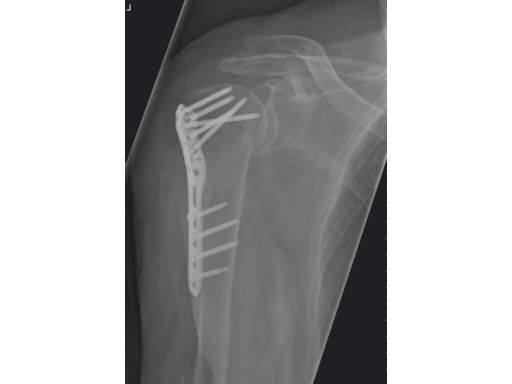

A 76-year-old woman suffered a low-energy fall at home.

Case provided by Stefaan Nijs, Leuven, Belgium